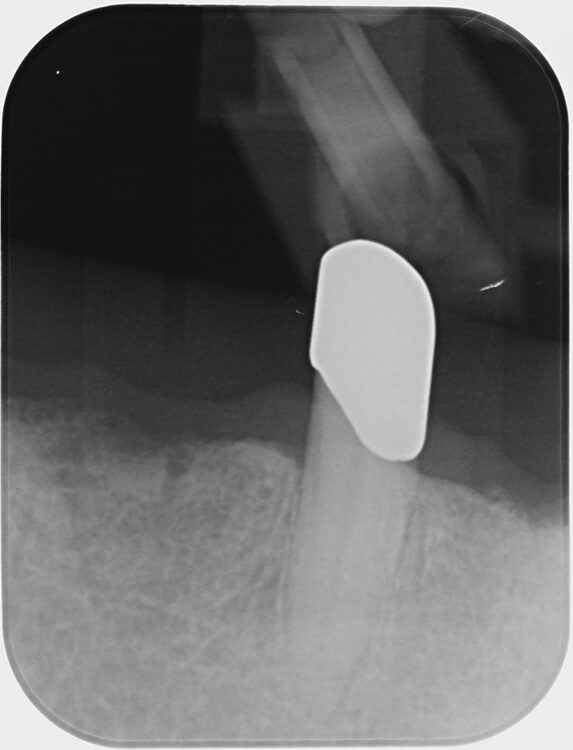

Abb. 6 a–h: Klinische und radiologische Dokumentation 7 Monate nach der AIT und der Applikation von Straumann® Emdogain® an den Zähnen 13 und 23. Die Sondierungstiefen und die parodontal entzündete Wundfläche haben sich im Vergleich zu den initialen Befunden deutlich reduziert. Es lagen keine Sondierungstiefen >5 mm vor. Das bedeutet, es bestand zu diesem Zeitpunkt keine Indikation für ein weiteres ggf. chirurgisches Vorgehen.Walter

Abb. 6 a–h: Klinische und radiologische Dokumentation 7 Monate nach der AIT und der Applikation von Straumann® Emdogain® an den Zähnen 13 und 23. Die Sondierungstiefen und die parodontal entzündete Wundfläche haben sich im Vergleich zu den initialen Befunden deutlich reduziert. Es lagen keine Sondierungstiefen >5 mm vor. Das bedeutet, es bestand zu diesem Zeitpunkt keine Indikation für ein weiteres ggf. chirurgisches Vorgehen.

Die klinische und radiologische Untersuchung nach der AIT und der Applikation von Straumann® Emdogain® an den Zähnen 13 und 23 erfolgte nach 7 Monaten. Die Sondierungstiefen und die parodontal entzündete Wundfläche hatten sich deutlich reduziert (Abb. 6). Es lagen keine Sondierungstiefen >5 mm mehr vor. Auch radiologisch konnten Umbauvorgänge und Kortikalisierungen auf den Einzelbildern im Vergleich zur initialen Panoramaschichtaufnahme festgestellt werden. Somit bestand zu diesem Zeitpunkt keine Indikation für ein weiteres ggf. parodontalchirurgisches Vorgehen.